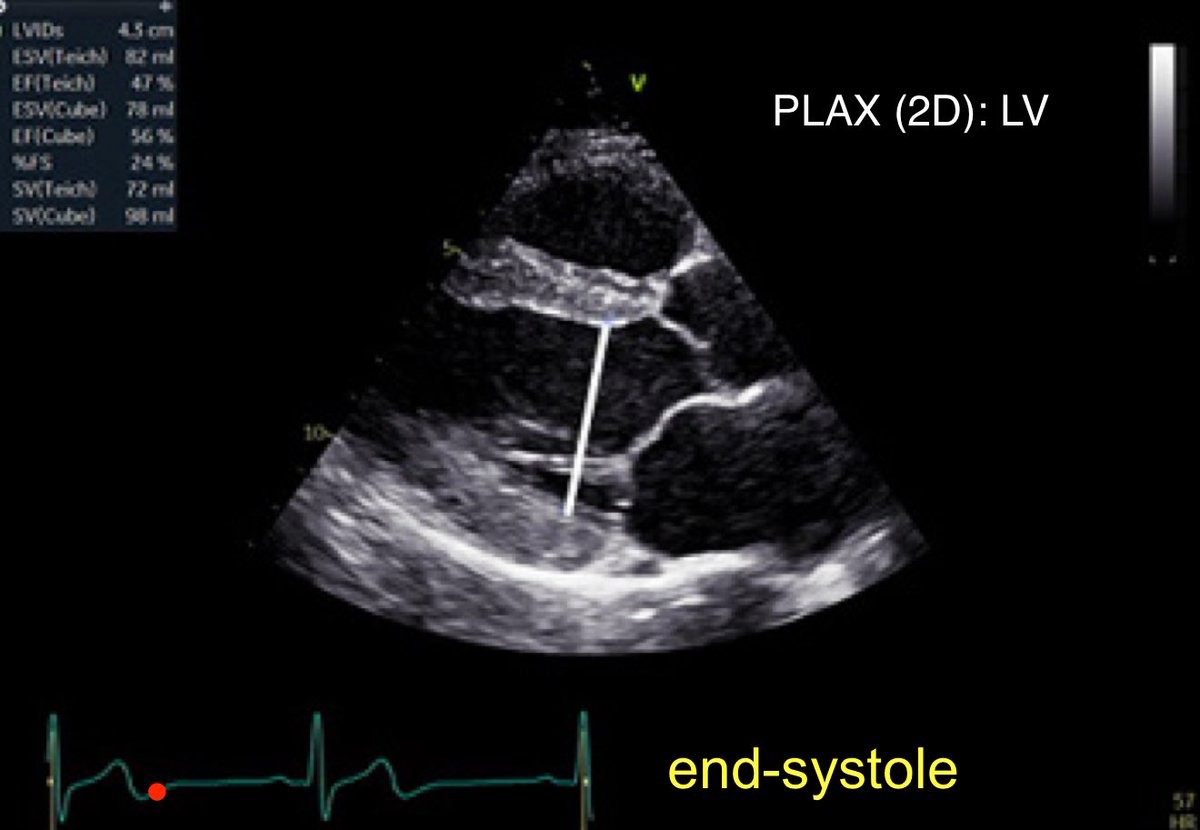

5/365 #firstecho #POCUS #VeXUS Left ventricular (LV) wall thickness and internal ∅ measures performed at end-diastole and end-systole 👇(PLAX)

POCUSpeek's tweet image. 5/365 #firstecho #POCUS #VeXUS

Left ventricular (LV) wall thickness and internal

∅ measures performed at end-diastole and end-systole 👇(PLAX)